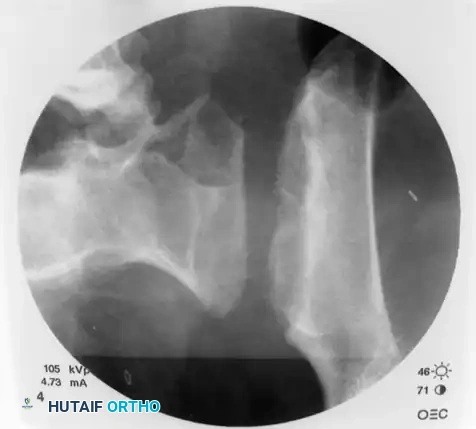

Once the trajectory is perfected, advance the guidewire under power across the sacroiliac joint and into the sacral ala.

Stop advancing just before the midline. Confirm safe passage on both the inlet and outlet views.

Finally, check the lateral sacral view to ensure that the guidewire is entirely contained within the osseous boundaries of the sacral body and has not breached the anterior alar slope.